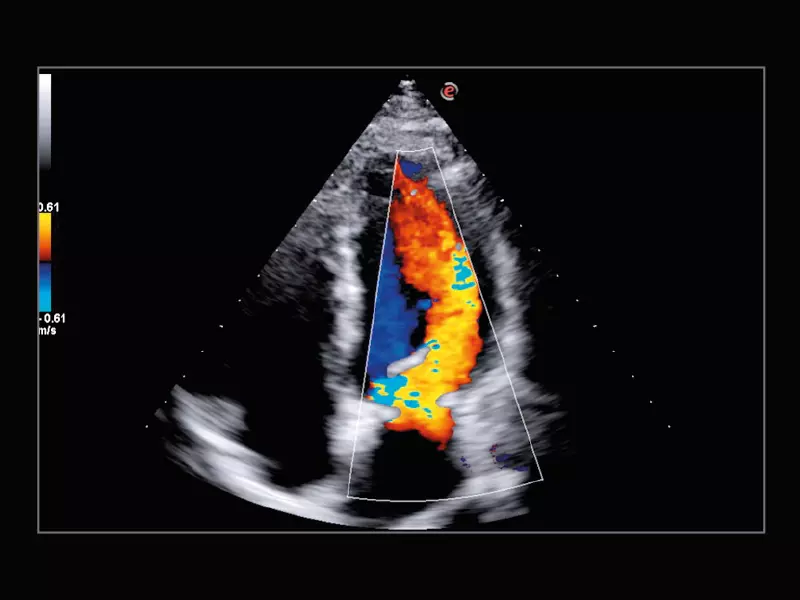

Q7 - Cardio CFM

Q7 - Cardio CFM